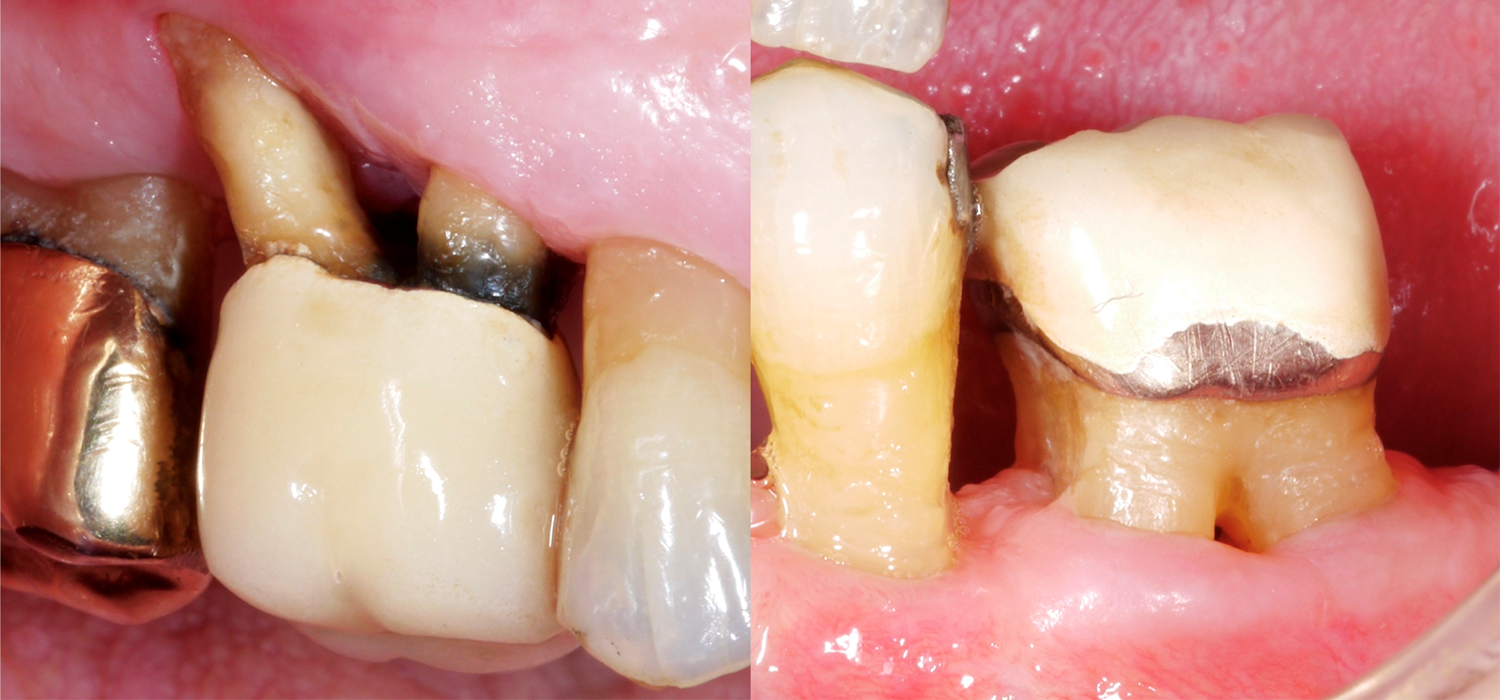

When it comes to teeth, those with multiple roots are, of course, often much more difficult to treat, especially if they present furcation defects. Why is the furcation area so challenging? In comparison to single-rooted teeth, access for mechanical cleaning of the root surface is much more difficult, the furcation entrance can often be very small/narrow, and there may also be further anatomical particularities, such as enamel projections.

A recently published study from Frankfurt (Eickholz 2021) specifically looked at teeth with a through-and-through furcation defect. They studied a total of 265 teeth with a through-and-through furcation defect in 160 patients; all patients had been receiving periodontal maintenance treatment for at least five years. We should take the following important points into account based on this data:

- Teeth with a grade III furcation defect are more frequently lost than single-rooted teeth, for example, and, after approx. 10 years of periodontal maintenance treatment, we should expect approx. one third of these teeth to have been extracted. At the same time, however, this also means that two thirds of these periodontally severely compromised teeth are still in place.